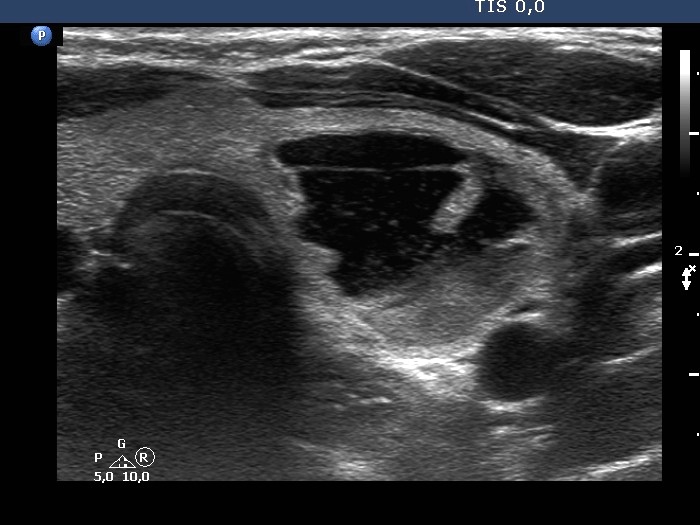

The composition of the nodule - case 636 (ultrasonographic picture 2)

Right lobe, longitudinal scan